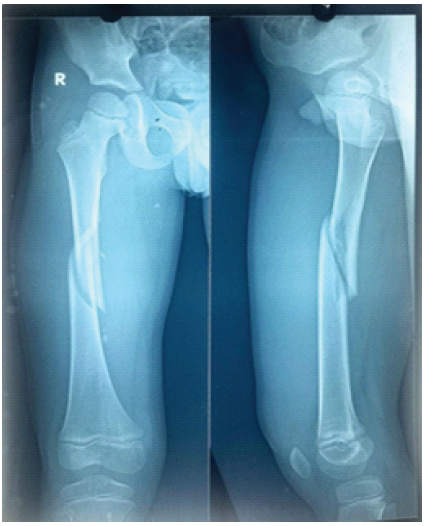

Post-operatively, patients were followed for 6 months with evaluations at 6, 12, and 24 weeks. Partial weight bearing was started at 6 weeks and gradually increased to full weight bearing once radiographic evidence of fracture union was observed on anteroposterior and lateral X-rays. During follow-up, patients were assessed for the time to fracture union, the occurrence of complications, such as superficial or deep infections, implant prominence or migration, fracture angulation, loss of reduction, fracture collapse, limb shortening, and range of motion. In addition, at the past follow-up, an orthoroentgenogram (scanogram) was performed to check whether there was limb length discrepancy (LLD). Pain, malalignment, LLD, and complications were reported and classified according to Flynn’s criteria. Ethical clearance was taken from the institute. In the image, Fig. 1 is showing mid 1/3rd shaft of femur fracture. Fig. 2 & 3 is showing immediate post-operative X-ray. Fig. 4 shows 2 years of follow-up, and Fig. 5 shows the X-ray after hardware extraction.

Figure 1: Immediate after trauma.